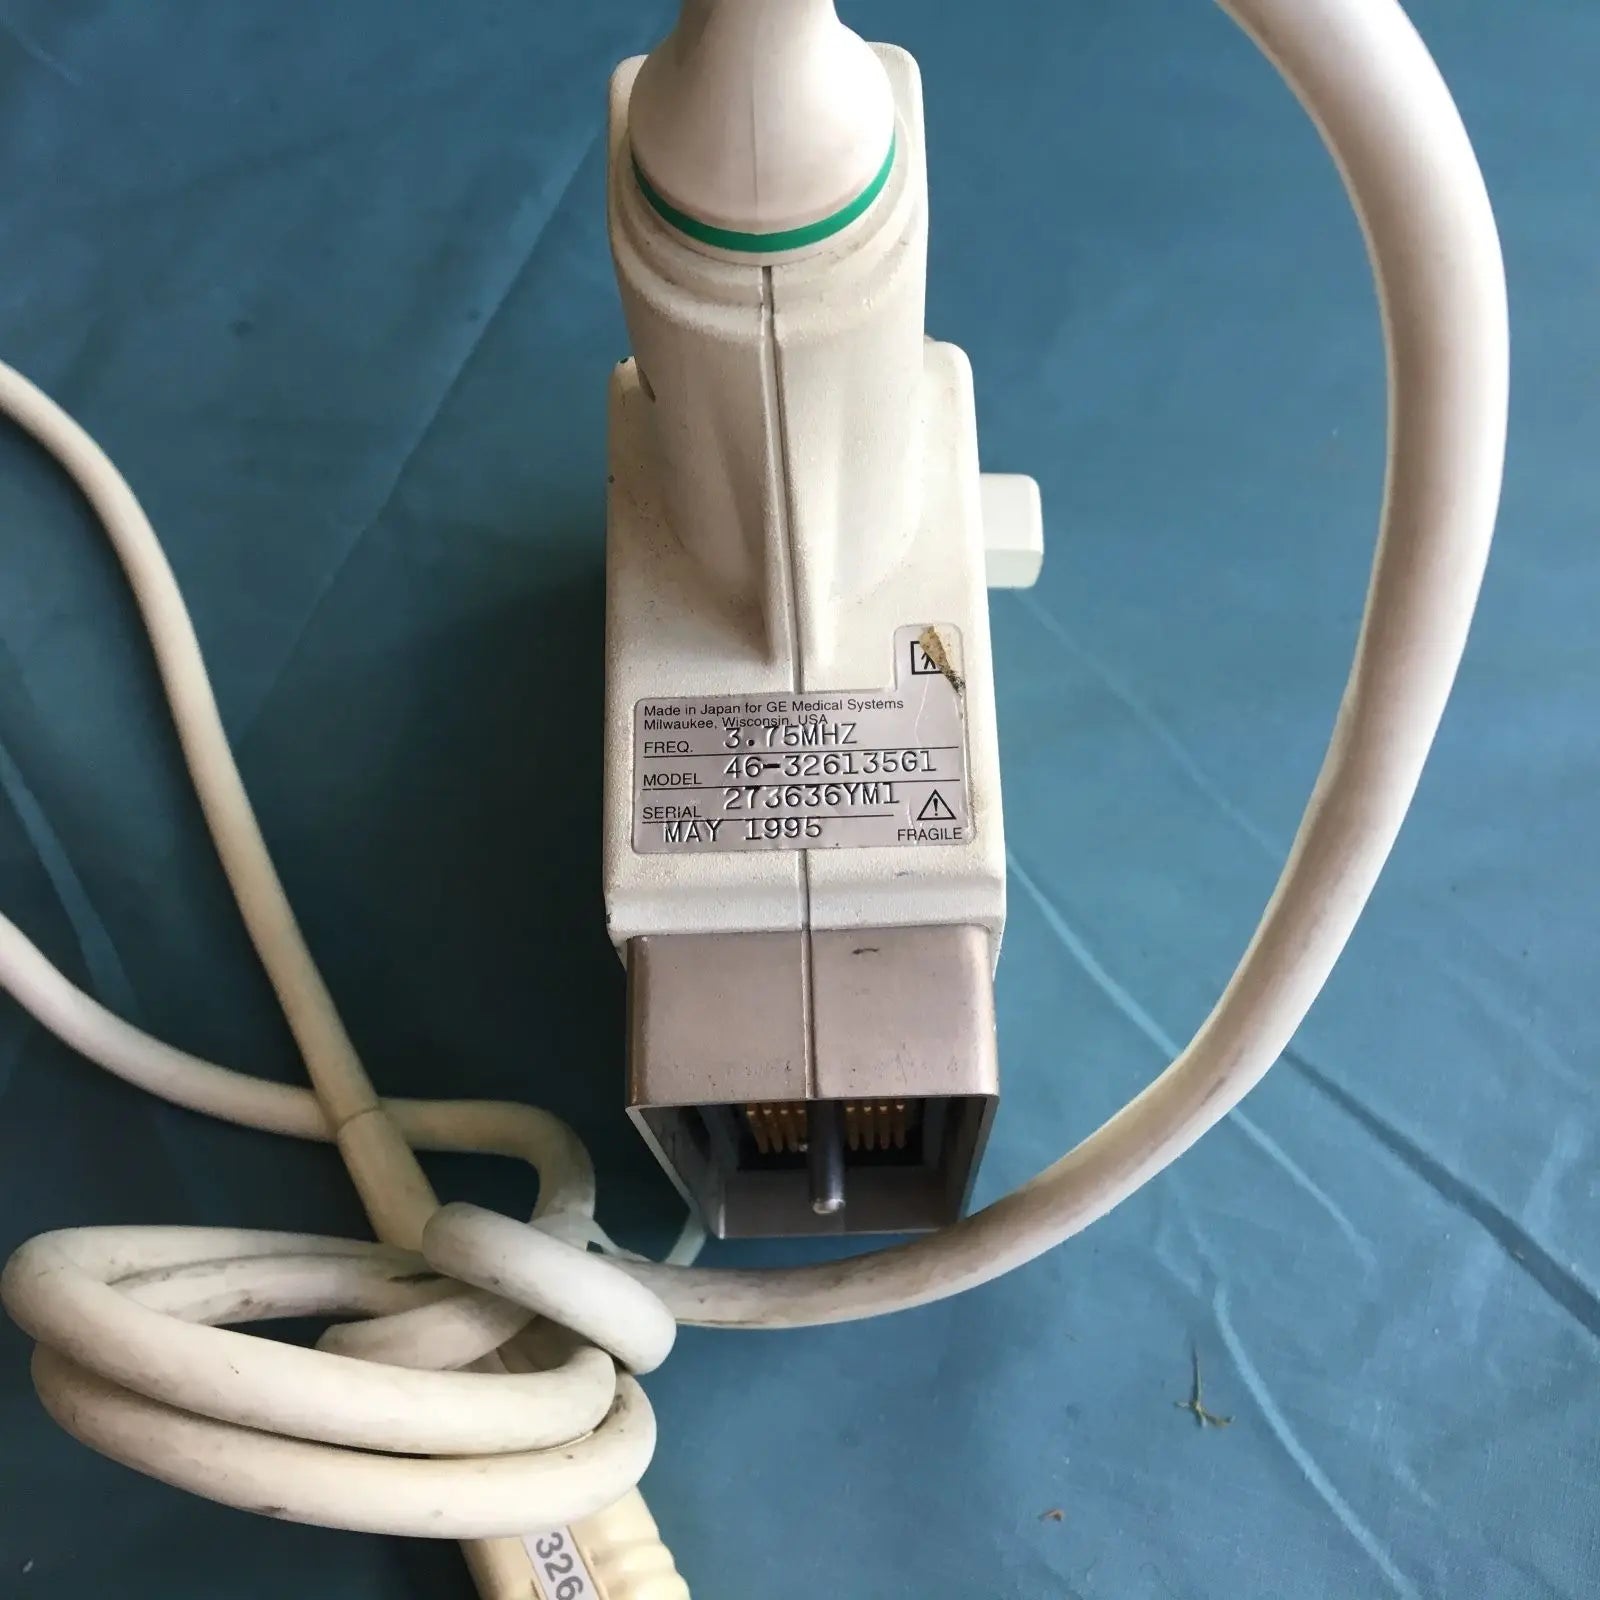

DIAGNOSTIC ULTRASOUND MACHINES FOR SALE

GE 348C 2197480 ULTRASOUND TRANSDUCER PROBE

Sale price$ 3,599.78